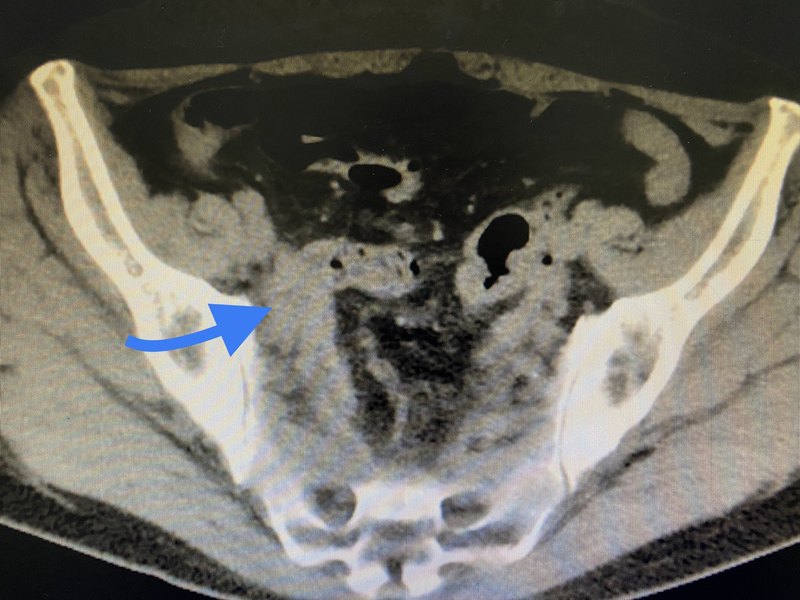

膀胱瓣治疗输尿管下段缺损

对于输尿管下段缺损较多、无法直接做膀胱再种的病例,膀胱瓣成形是非常适合的手术方式。如此例患者,距输尿管开口5cm位置完全梗阻,切除狭窄段后无法直接再种于膀胱。于是取膀胱瓣卷成5cm长管道再与输尿管无张力吻合,手术效果满意。